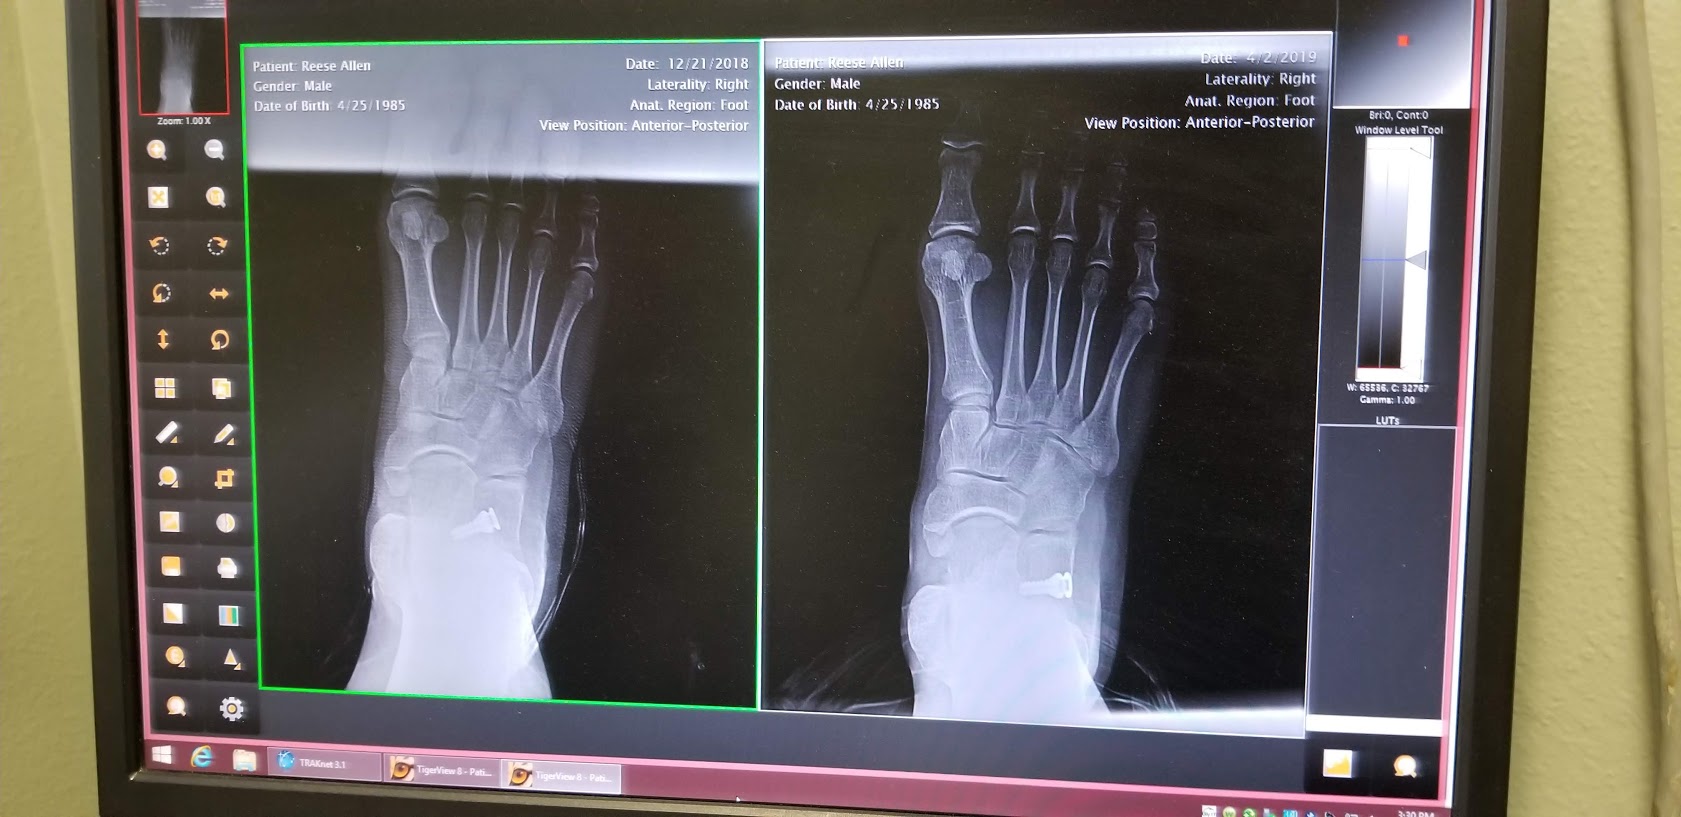

I went in on Tuesday, April 2nd, and had my right foot X-rayed. Unfortunately, the implant had backed out considerably since the day of the procedure.

It was still in the joint far enough to be having a beneficial effect, but it was well out of place from where it needed to be to provide the best result. After some discussion we decided that it would be best to try to re-seat the implant properly, both so that it would be more effective and so that it would be less likely to back out even further and eventually become ineffective. The left foot surgery scheduled for the following week became a right foot re-do surgery on the same day, and we decided to delay the left foot surgery indefinitely until we see how the right goes.

This time, the doctor did a bit more cutting and was then able to drive the implant deeper into the cavity between the talus and calcaneus bones. Preliminary X-rays showed good placement, so he stitched me back up. We then took X-rays with me standing on the freshly-repaired foot which clearly show that the implant is now much deeper than the first attempt from December.